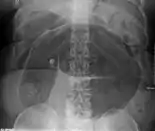

After taking a thorough history, the diagnosis of colonic volvulus is usually easily included in the differential diagnosis. Abdominal plain x-rays are commonly confirmatory for a volvulus, especially if a "bent inner tube" sign or a "coffee bean" sign are seen. These refer to the shape of the air-filled closed loop of colon which forms the volvulus. Should the diagnosis be in doubt, a barium enema may be used to demonstrate a "bird's beak" at the point where the segment of proximal bowel and distal bowel rotate to form the volvulus.

This area shows an acute and sharp tapering and looks like a bird's beak. If a perforation is suspected, barium should not be used due to its potentially lethal effects when distributed throughout the free intraperitoneal cavity. Gastrografin, which is safer, can be substituted for barium.